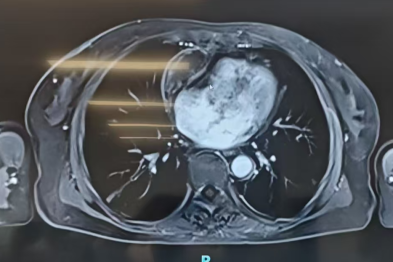

腹水缠身三载求医路尽 心脏巧解难题绝处逢生

2026-04-21 -